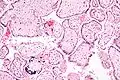

- Placentitis por citomegalovirus (CMV)